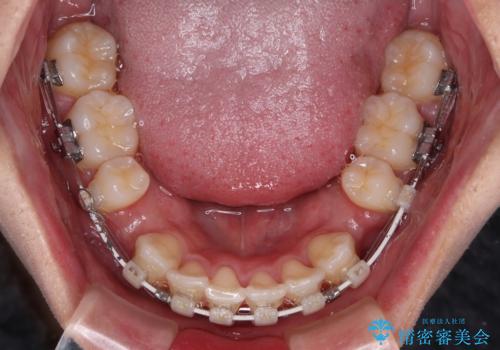

- 矯正装置

- 審美装置

- 2年2ヶ月

- 治療回数

- 10-30回